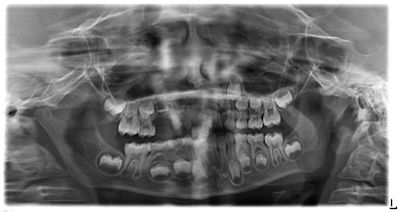

6.5-year-old girl with an unusual radiographic finding

A 6.5-year-old girl presented to the pediatric dentist with her parents because of an unusual radiographic finding in the anterior maxilla.